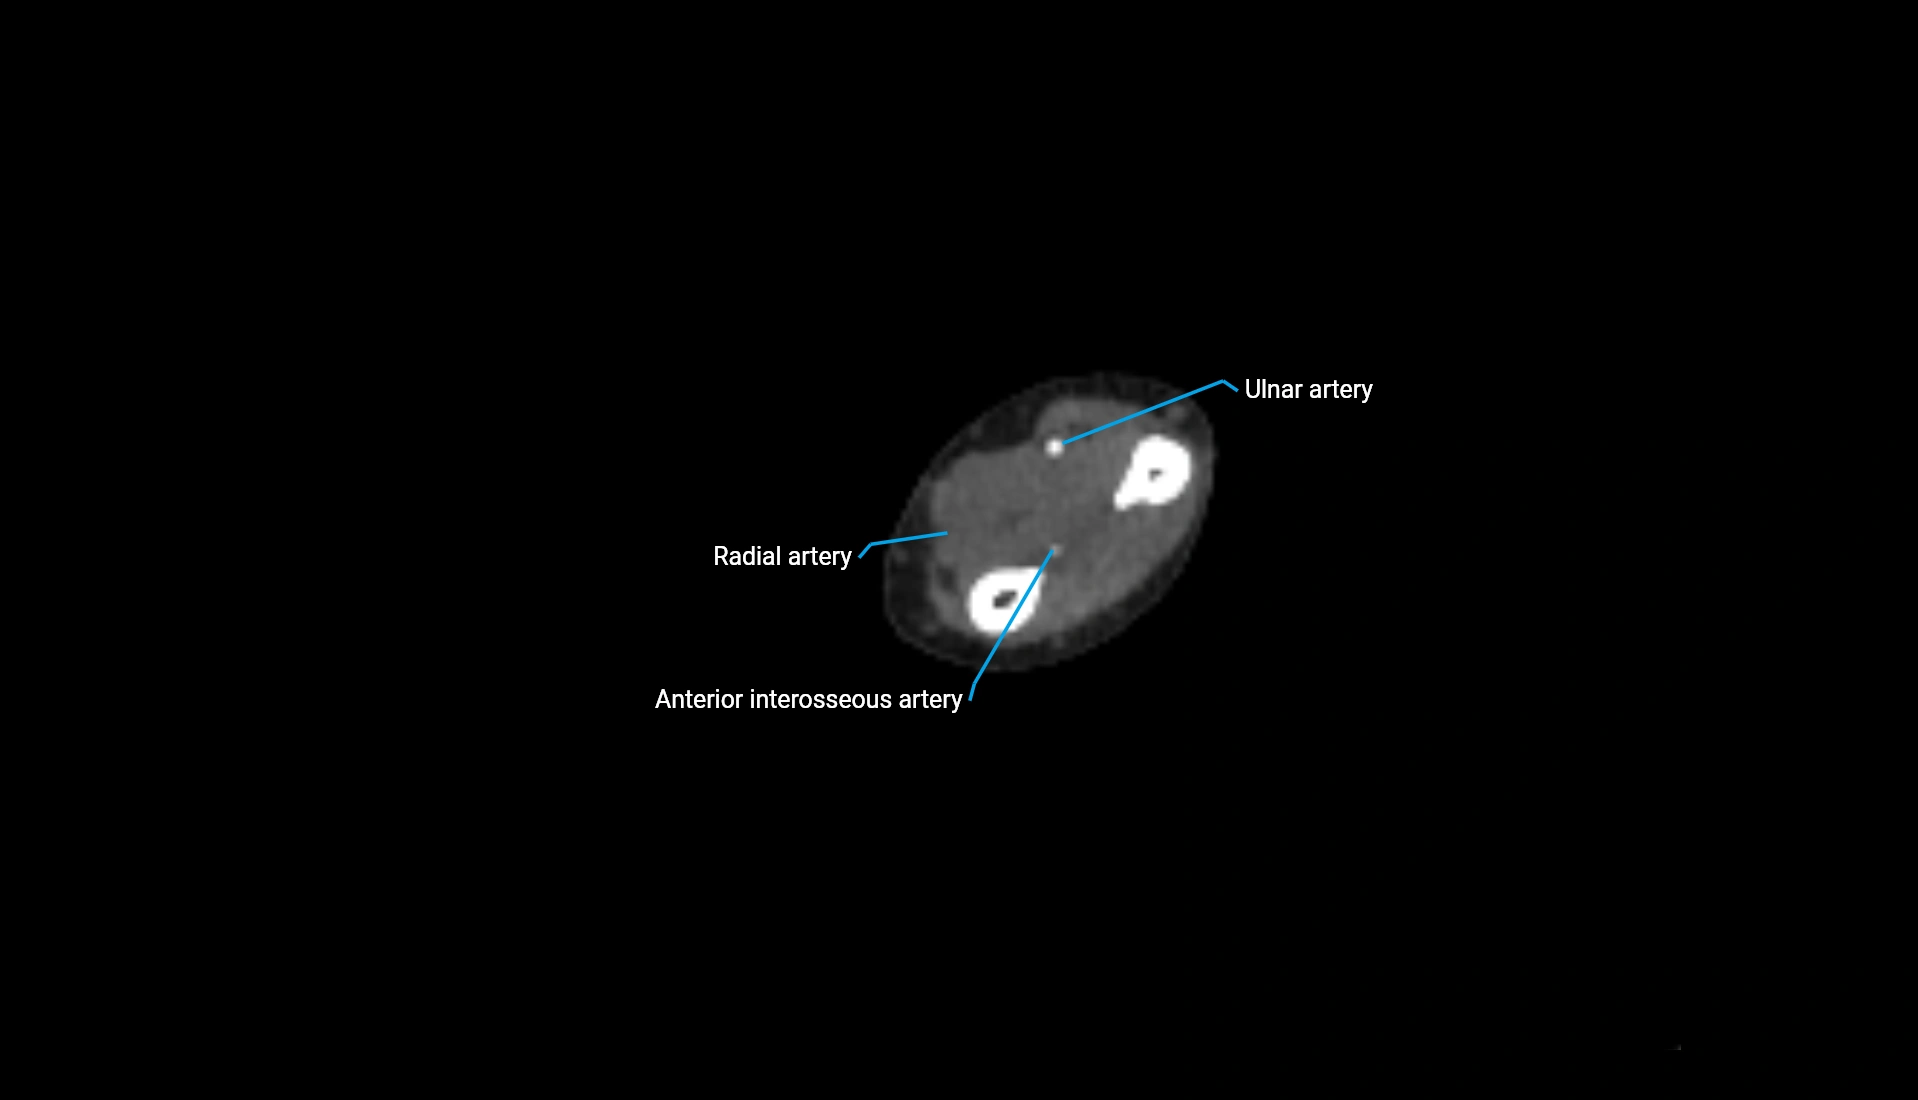

CT Appearance

Non-Contrast CT:

• Cortex: High-density, sharply defined

• Subchondral bone: Dense cancellous matrix

• Articular surface: Smooth concave contour articulating with the capitellum

• Excellent for evaluating bone integrity, alignment, and subtle fractures